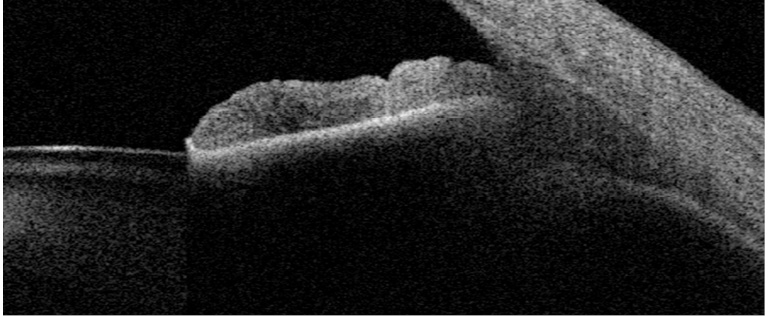

Anterior segment OCT imaging has been used for anatomical evaluation and for clinical diagnosis, but also contact lens fitting and phakic intraocular lens implantation are also two areas that have been benefited from this technology. Mainly, non-contact OCT has been applied for measuring different ocular parameters on the anterior segment. Specifically, corneal thickness (2), anterior chamber depth (ACD) (3), white-to-white (3) and angle assessment (4) have been measured and evaluated under different conditions and populations. In addition to these measurements, other parameters, such as ciliary muscle area and lens thickness or lens curvature have been also determined (Figure 1). Accurate measurements of these parameters in the eye are extremely useful both for clinical diagnosis and applications, and also for basic research to understand how they eye works. This may help to develop future solutions for the aging eye, new optical designs for intraocular lenses, and to understand the emmetropization process in the human eye, for instance.

figure1